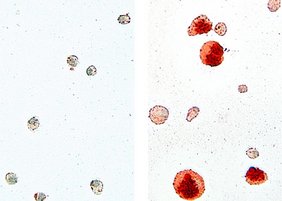

Alveolarmakrophagen isoliert aus der Lunge von Wildtyp Mäusen (links) und Cebpb-defizienten Tieren (rechts). Zellen ohne Cebpb sehen im Vergleich groß und aufgebläht aus, darin lagern sich viele Lipide ab (rot). AG Leutz, MDC

„Wir haben Alveolarmakrophagen von gesunden Mäusen und solchen, denen das Gen für C/EBPb fehlt, isoliert und in vitro-Tests sowie diverse Genom- und Transkriptomanalysen durchgeführt“, erklärt Erstautorin Dr. Dorothea Dörr. Konkret hat die Forscherin die biologischen und molekularbiologischen Eigenschaften der Alveolarmakrophagen untersucht. Sprich: wie gut sie in der Lage sind, Lipide aufzunehmen und zu verstoffwechseln. Während die Makrophagen gesunder Mäuse ordentlich ihre Arbeit verrichteten, nahmen die der genveränderten Mäuse zwar sehr viel Lipid auf und speicherten es – konnten es aber nicht mehr verdauen. Die Fresszellen quollen schaumartig auf, gingen bald zugrunde und die Lipide lagerten sich vermehrt ab. Genauso, wie Mediziner*innen es von der Lungenkrankheit PAP kennen. Außerdem konnten sich die defekten Makrophagen kaum noch vermehren.